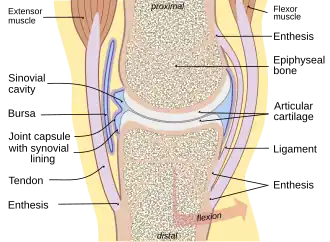

| Typical joint showing the entheses | |

Enthesitis is inflammation of the entheses (singular: enthesis), the sites where tendons, ligaments and joint capsules attach to bones.[1][2]